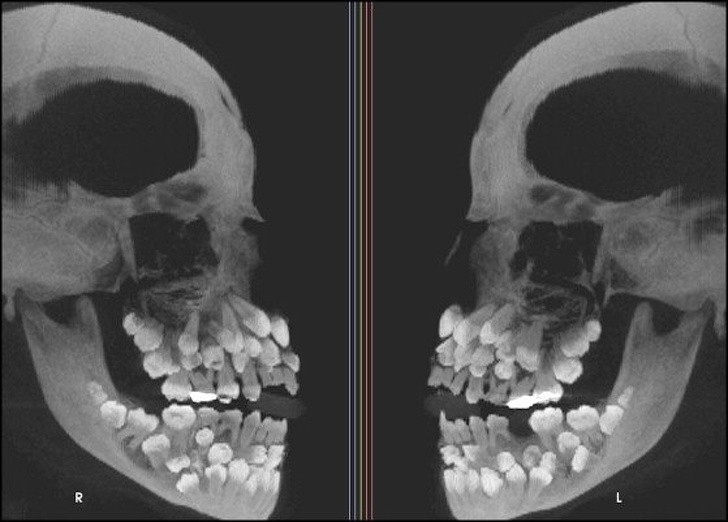

Ljudje smo resnično čudna bitja in se nam lahko zgodijo neverjetno bizarne stvari. Ti rentgenski posnetki bodo šokirali tudi tiste, ki mislijo, da so videli že vse.

Radiologi so tako že precej navajeni, da na rentgenskih posnetkih vidijo čudne stvari in nekatere izmed teh, ki smo jih za vas zbrali v galeriji, jih sploh niso presenetile. Tukaj je 15+ odštekanih in na trenutke šokantnih rentgenskih posnetkov.